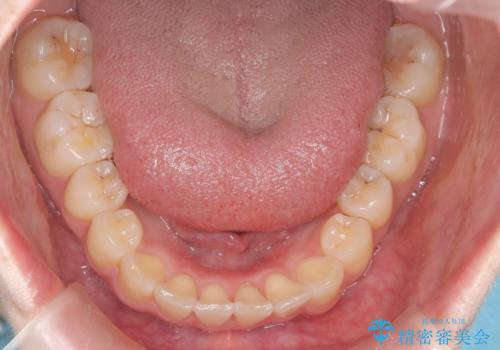

前歯のガタつきをマウスピース矯正で改善

- 前歯のガタツキが気になると来院されました。

マウスピース矯正治療を選択しました。

奥歯の噛み合わせは綺麗に噛んでいたため、前歯の叢生(でこぼこ)に集中して治療するように計画しました。